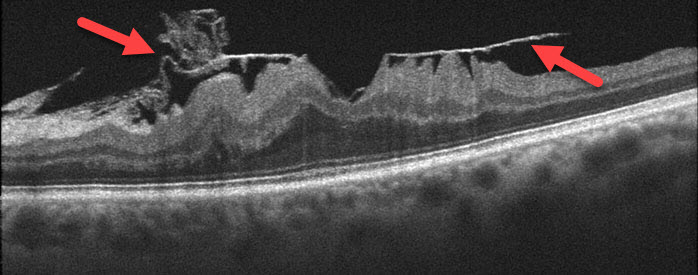

Macular pucker (also referred to as preretinal fibrosis, epiretinal membrane, or cellophane maculopathy) consists of a cellophane-like membrane that grows over and mechanically “puckers” and distorts the macula.

You can’t diagnose macular pucker by looking in the mirror since your eye will usually look and feel normal. The diagnosis is made with a thorough retinal examination through a dilated pupil, OCT scanning, and fluorescein angiography.